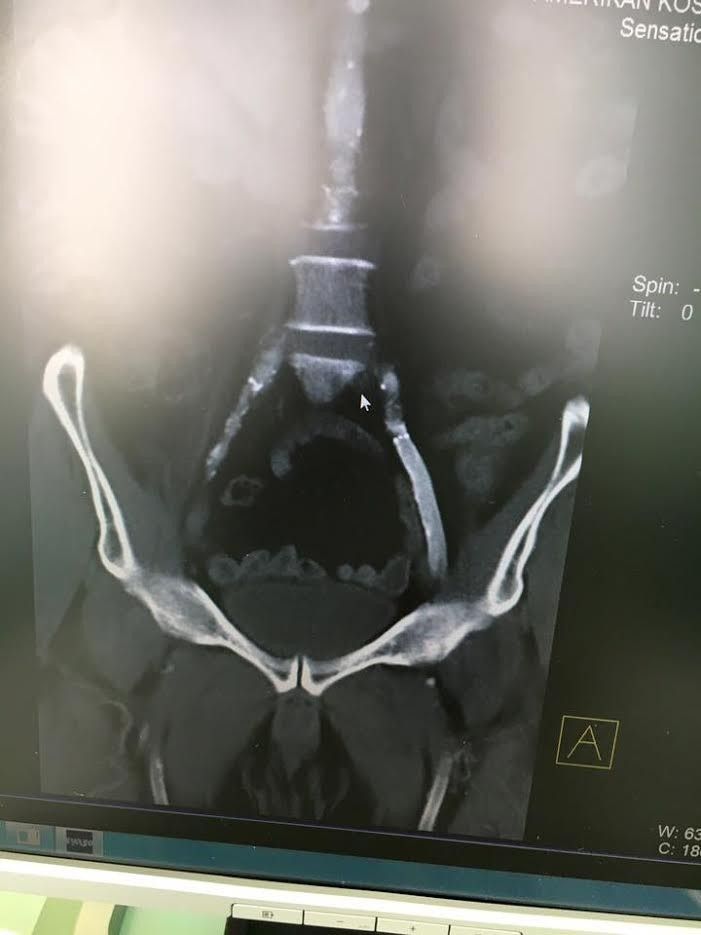

| Ky është suksesi i radhës nga Departamenti i Kirurgjisë Vaskulare të Spitalit Amerikan Posted: 01 Sep 2016 04:58 AM PDT Pacienti, shqiptar i emigruar prej vitesh në SHBA, kishte shkuar në Spitalin Amerikan në gjendje të rëndë shëndetësore dhe, pas ekzaminimeve, urgjentisht i ishte nënshtruar ndërhyrjes kirurgjikale nga stafi i Kirurgjisë Vaskulare të Spitalit Amerikan. Pacientit i është bërë hapja e stentit periferik të thrombozuar (mbyllur) në gjithë aksin e arterieve të ekstremitetit (këmbës), pa i dëmtuar stentet, procedurë e cila është realizuar me sukses në Spitalin Amerikan nga Dr. Elmi Olluri – Kirurg Vaskular, me ndihmën e ekipit asistues në sallë. Këto stente pacientit i janë vendosur në SHBA para disa viteve. Një procedurë e tillë e realizuar në kohë urgjente dhe me profesionalizëm, rezultoi me shpëtimin e këmbës nga amputimi, amputim i cili në qendrat e rajonit do të ndodhte thuajse 100 për qind. Por, falë profesionalizmit dhe përvojës arrihet që edhe stentet të hapen me sukses. Kjo dëshmon edhe njëherë se Kirurgjia Vaskulare e Spitalit Amerikan me ekipin e mjekëve Dr. Elmi Olluri dhe Dr. Halil Krasniqi është një qendër referente jo vetëm në Kosovë, por edhe në rajon e më gjerë. Spitali Amerikan, Përqafoje jetën! /Telegrafi/ The post Ky është suksesi i radhës nga Departamenti i Kirurgjisë Vaskulare të Spitalit Amerikan appeared first on Telegrafi. |